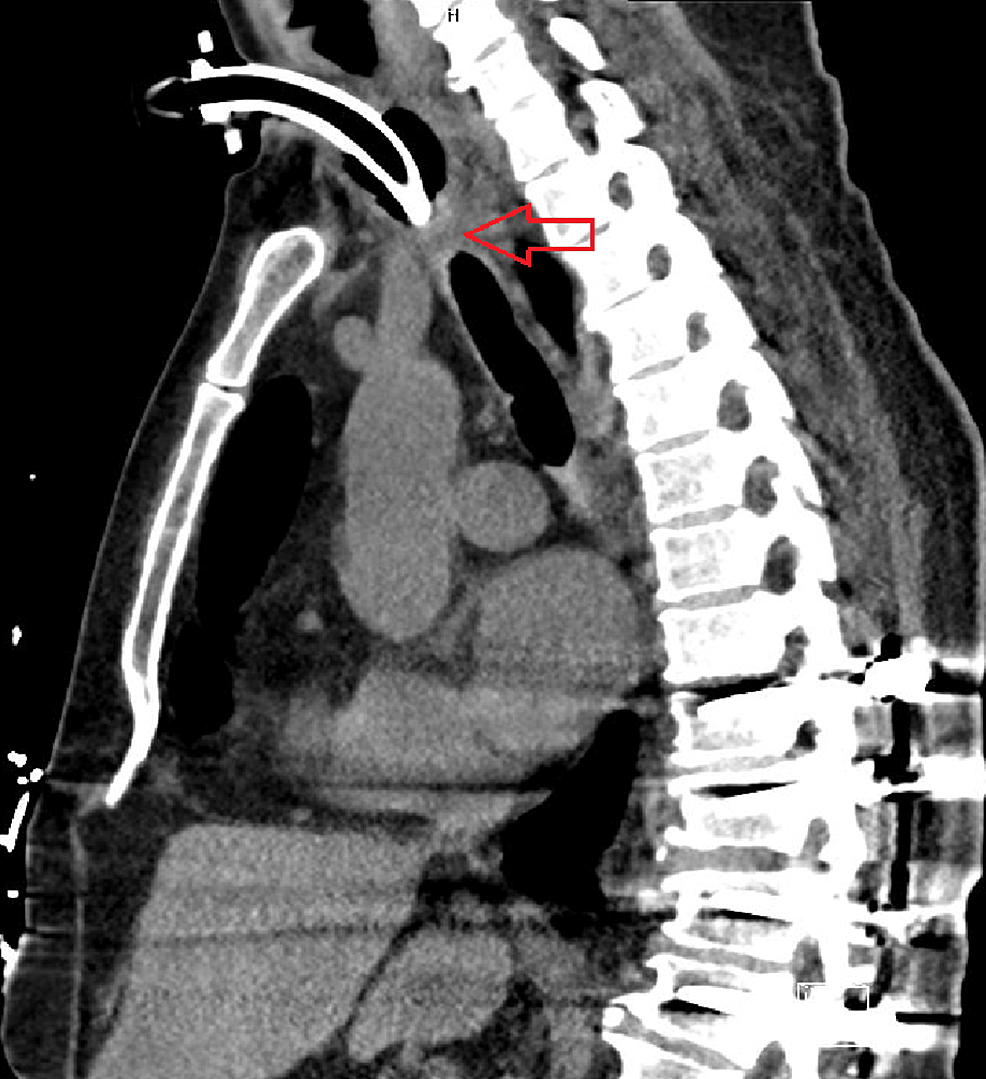

From www.ctisus.com

Tracheal Stenosis due to Prior Tracheostomy Chest Case Studies Tracheal Stenosis Tracheostomy tracheostomy can be performed as a surgical or percutaneous procedure. surgical variables associated with increased stenosis included placement of a tracheostomy tube greater than size. severe post tracheostomy (pt) and post intubation (pi) tracheal. it can develop when scar tissue forms in a person’s trachea due to prolonged intubation — when a breathing tube is inserted. Tracheal Stenosis Tracheostomy.

Tracheal Stenosis due to Prior Tracheostomy Chest Case Studies Tracheal Stenosis Tracheostomy surgical variables associated with increased stenosis included placement of a tracheostomy tube greater than size. severe post tracheostomy (pt) and post intubation (pi) tracheal. tracheostomy can be performed as a surgical or percutaneous procedure. it can develop when scar tissue forms in a person’s trachea due to prolonged intubation — when a breathing tube is inserted. Tracheal Stenosis Tracheostomy.